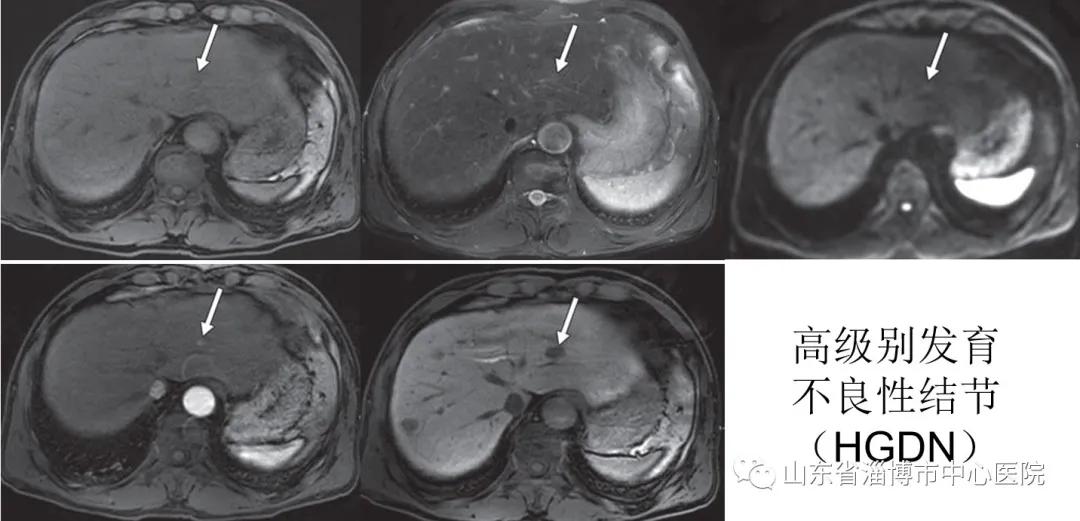

肝细胞癌(HCC)是最常见的肝脏原发性恶性肿瘤,发病率呈逐年递增的趋势,死亡率高,对人类健康构成了严重威胁。HCC是一个连续的、多阶段的病理过程,肝硬化结节性病变经过肝硬化再生结节(RN)、低级别发育不良性结节(LGDN)、高级别发育不良性结节(HGDN)、DN癌变演变成小肝癌(≤2cm)、典型肝癌。因此,早期准确诊断小肝癌甚至HGDN并及时采取治疗措施,是提高患者生存率、改善预后的关键。不典型肝癌、肝脏局灶性结节增生(FNH)、肝腺瘤等疾病的鉴别诊断也是影像学的难点。

以往临床上对HCC的检出,主要依靠超声、CT或Gd-DTPA动态增强MRI扫描,其敏感性主要依赖HCC的动脉、门静脉血供变化,即典型的“快进快出”表现,诊断才能确立,对于HGDN、部分小HCC,由于其血供变化不明显或乏血供而很难被检出。钆塞酸二钠(Gd-EOB-DTPA)为MRI肝脏特异性对比剂(肝细胞特异性摄取率高达约50%),同时具有非特异性细胞外对比剂和肝胆特异性对比剂的特性,在得到与非特异性对比剂相似的多期动态增强效果的同时,还可以通过独有的肝胆期来鉴别病灶内是否含有功能的肝细胞,对于肝脏疾病的诊断、鉴别诊断具有独特的优势。

对于超声、CT或Gd-DTPA增强MRI表现不典型的HCC,尤其是HGDN或小肝癌患者,可进一步行 Gd-EOB-DTPA增强MRI检查,有助于提高诊断准确性和信心。对于血AFP进行性升高,尤其伴有超高危因素(如乙型肝炎、丙型肝炎相关性肝硬化等),而其他影像检查(超声、CT或Gd-DTPA增强MRI)结果阴性的患者,推荐行Gd-EOB-DTPA增强MRI检查。